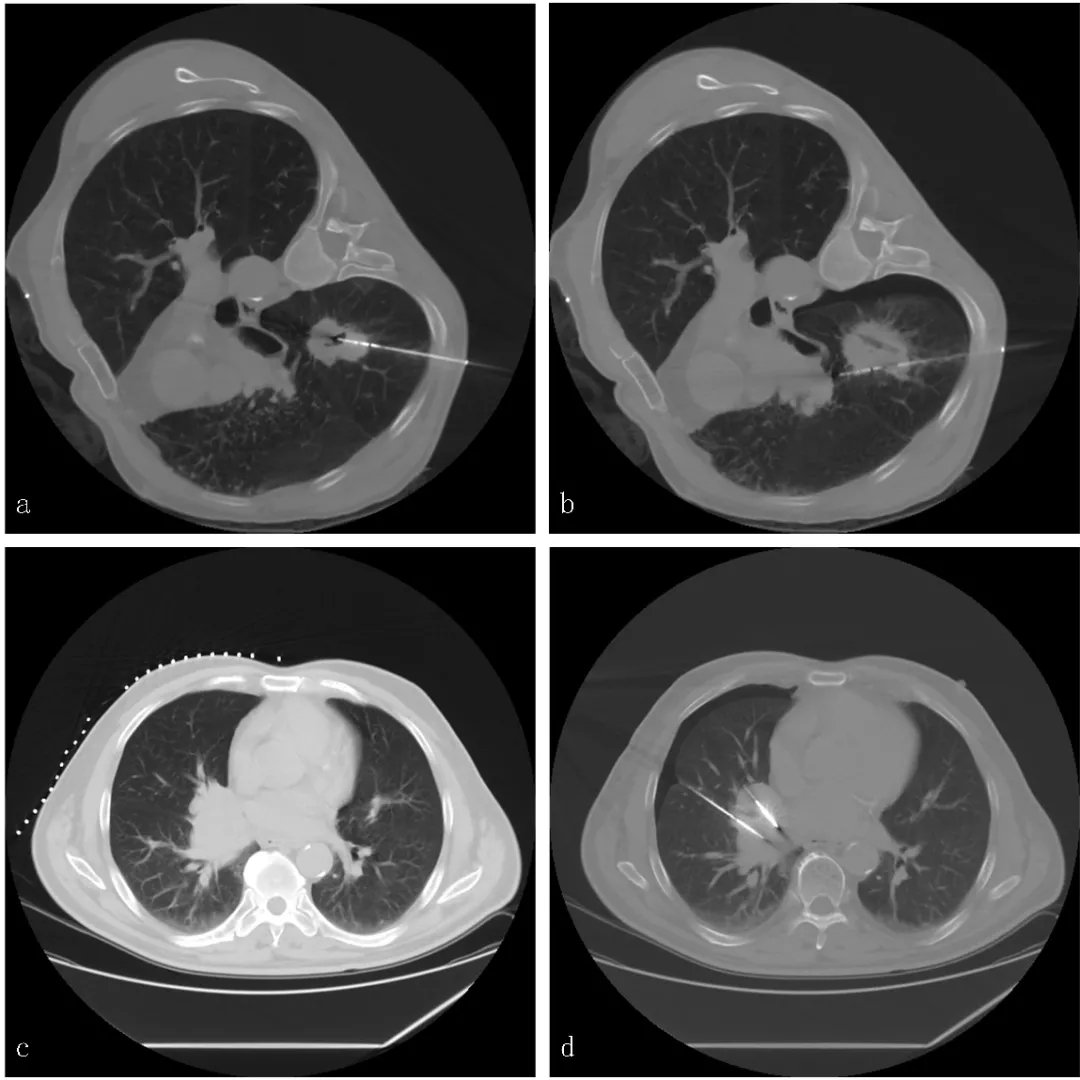

因此,北京医院肿瘤微创治疗中心创新性地使用同轴套管技术同步实施经皮肺穿刺活检及热消融治疗,应用于NSCLC患者的诊疗(图1)。该中心的研究显示,对比序贯活检及消融治疗高度可疑恶性肺结节,同轴套管活检同步消融术可出现更少的并发症并有类似的治疗效果。

图1. 经皮肺穿刺活检同轴套管微波消融术示例。a.MWA针与同轴套管组合(短箭头为消融针,长箭头为同轴套管);b.同轴套管组合原件包括:全自动活检枪、套管针、套管针芯及MWA针;c. CT引导下同轴套管穿刺入病灶内;d.活检后MWA针经同轴套管穿入病灶内实施消融治疗。